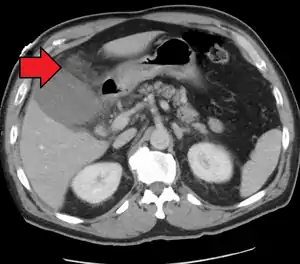

| Acute cholecystitis as seen on CT. Note the fat stranding around the enlarged gallbladder. | |

Right upper quadrant abdominal ultrasound is most commonly used to diagnose cholecystitis.[1][25][26] Ultrasound findings suggestive of acute cholecystitis include gallstones, pericholecystic fluid (fluid surrounding the gallbladder), gallbladder wall thickening (wall thickness over 3 mm),[27] dilation of the bile duct, and sonographic Murphy's sign.[13] Given its higher sensitivity, hepatic iminodiacetic acid (HIDA) scan can be used if ultrasound is not diagnostic.[13][14] CT scan may also be used if complications such as perforation or gangrene are suspected.[14]

Acute cholecystitis with gallbladder wall thickening, a large gallstone, and a large gallbladder- Significant gallbladder wall thickening[28]